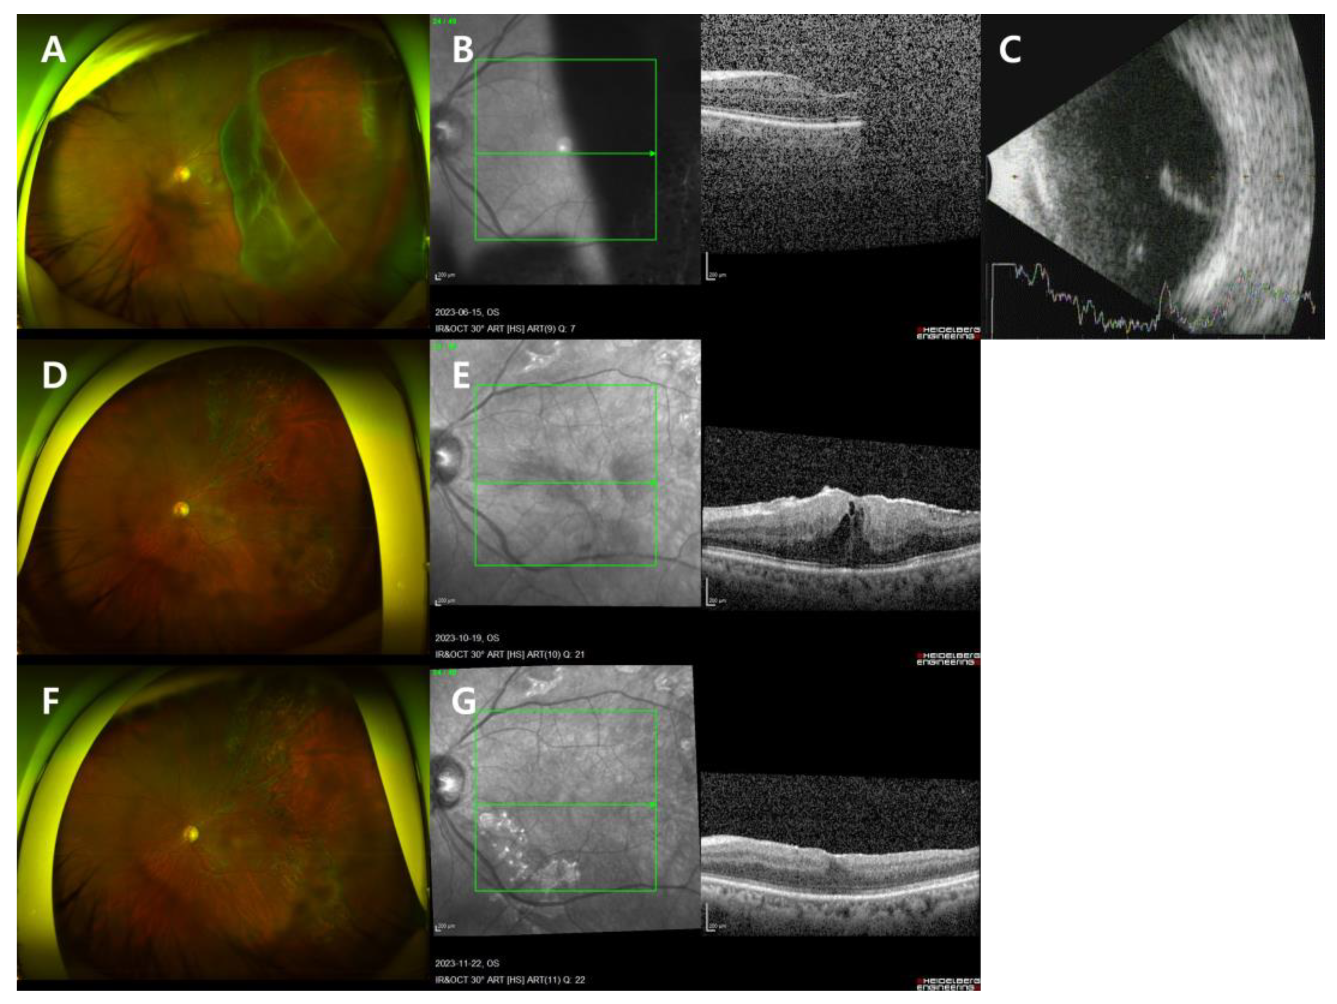

A 60-year-old man visited the clinic reporting floaters in the left eye that began 12 days prior and obscured vision that started the day before. He had a history of retinal tear in the right eye treated with barrier PC at a local ophthalmology clinic two years ago and had undergone cataract surgery in both eyes. There was no other medical history. Corrected visual acuity was 20/20 in the right eye and 20/100 in the left eye, with no significant findings in the anterior segment. FP, OCT, B-scan, and fundus examination revealed vitreous hemorrhage and GRT in the superotemporal direction with macula-off RRD in the left eye (Figure 3A–C). The axial length of the left eye was measured at 25.95 mm.

On the day of his visit, the patient underwent PPV, endolaser, fluid–air exchange, and intravitreal gas injection (C3F8 14%) in the left eye. The day after the surgery, his visual acuity in the left eye was hand motion, IOP was 11 mmHg, and the retina was well attached and flat. The patient maintained a prone position for three days post-surgery, followed by a right decubitus position.

Three months post-operation, the retina remained flat and well attached without complications, and the patient’s BCVA was 20/20. However, four months post-operation, a decrease in visual acuity in the left eye was observed along with the identification of a secondary epiretinal membrane (ERM). The patient underwent another surgery in the left eye, including PPV, endolaser, epiretinal membrane and internal limiting membrane peeling (ERM-ILMP), fluid–air exchange, and intravitreal gas injection (sulfur hexafluoride (SF6) 20%). Gas is not typically used in standard epiretinal membrane surgeries. However, this patient had RRD with GRT, and although the RRD with GRT was properly reattached, there remained a risk of retinal redetachment during manipulation. Given the patient’s high level of anxiety, and following a thorough discussion, we opted to use SF6 gas due to its shorter duration compared to C3F8 (Figure 3D,E).

Six months after the first surgery, the retina remained flat and free of ERM, and the patient’s BCVA was confirmed to be 20/20 without any complications (Figure 3F,G).

Figure 3. Case 3 patient’s left eye images. (AC) On the day of presentation. (A) FP showed RRD with GRT in the superotemporal direction. (B) OCT showed macula-off RD. (C) B-scan showed RD. (D,E) Four months after the initial surgery. (D) FP showed a secondary epiretinal membrane (ERM). (E) OCT showed a secondary ERM. (F,G) Six months after the initial surgery. (F) FP showed a flat, well-attached retina. (G) OCT showed a flat, well-attached retina.